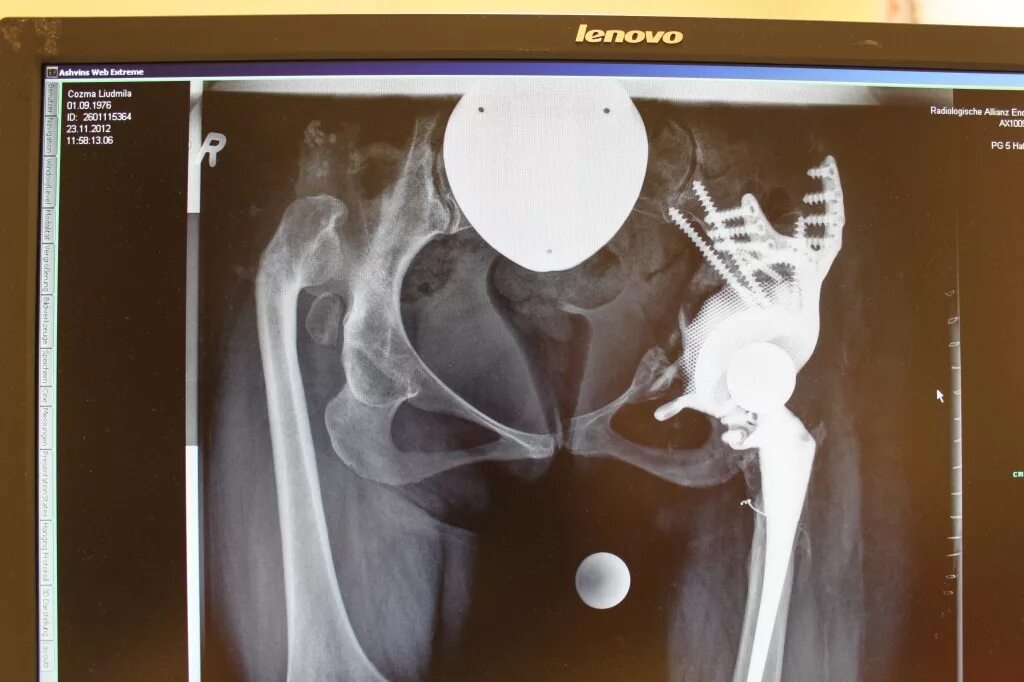

Протезы тазобедренных суставов по квоте